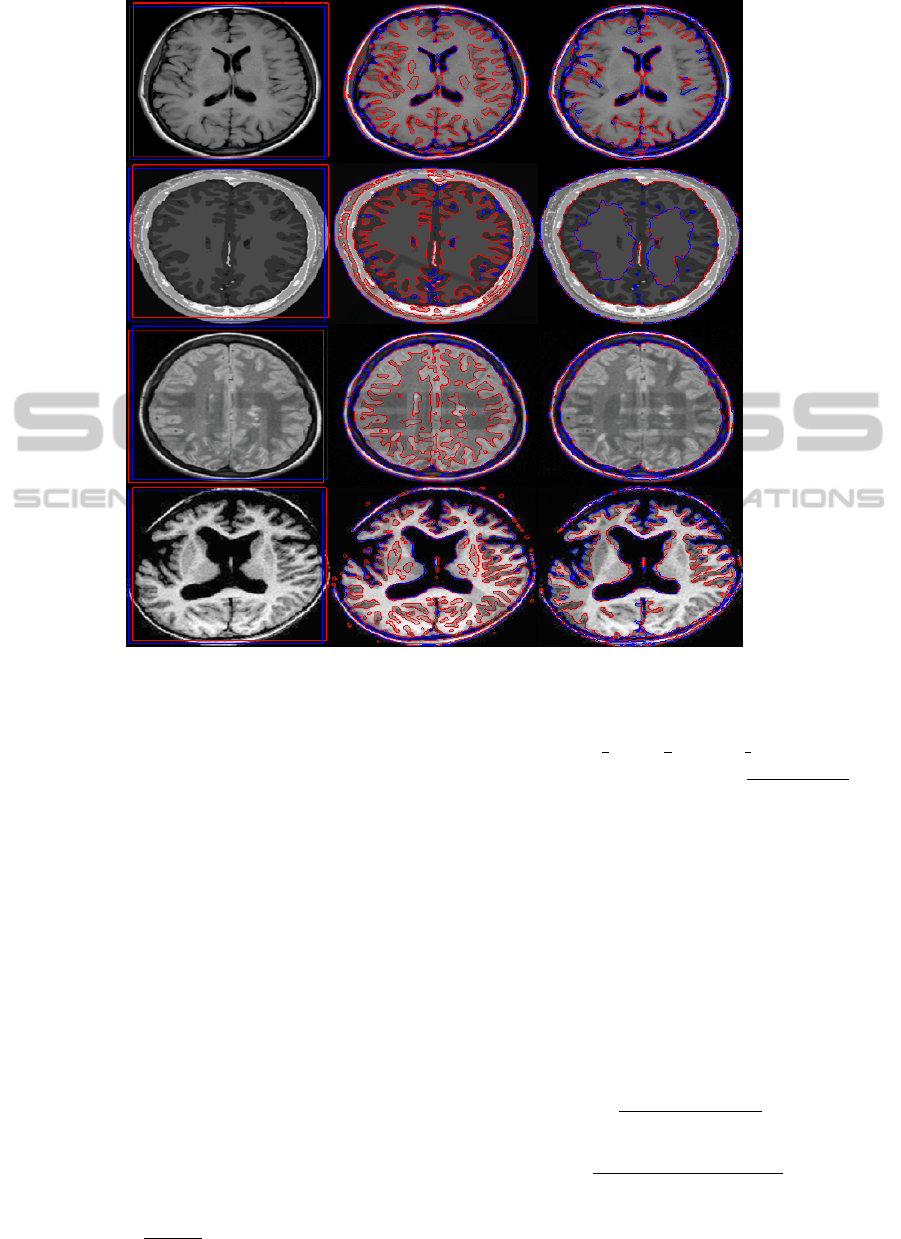

Segmentation of brain MRI images into distinct and

non-overlapping regions, such as WM, GM and CSF,

is a challenging problem due to the geometric com-

plexity of the regions to be segmented. The pres-

ence of noise and intensity inhomogeneity in the im-

age significantly increases the complexity of the prob-

lem. Since, there are three important regions (WM,

GM and CSF) in the brain area, a four-phase level

set method is necessary for segmenting the image into

three or four regions. This paper presents a four-phase

region based active contour method that segments an

MRI brain image into WM, GM and CSF regions with

a good accuracy. It uses both local and global inten-

sity averages in the definition of an energy functional,

such that local intensity mean values help the pro-

posed model to segment regions with intensity inho-

mogeneity, whereas global intensity mean values are

responsible for segmenting the homogeneous areas in

the image. In addition, a pixel correction method

based on simple thresholding is applied in order to

correct wrong pixels.